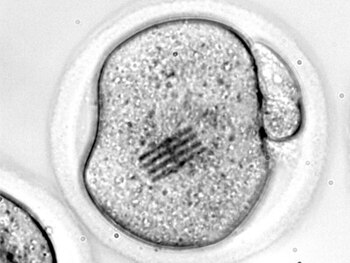

En los últimos años, la práctica de transferir embriones previamente congelados en tratamientos de reproducción asistida ha ido creciendo de forma progresiva, gracias a las mejoras introducidas en el laboratorio, como la vitrificación (un proceso que permite congelar material biológico de forma mucho más rápida y segura), y la optimización de los cultivos que facilitan el desarrollo del embrión en el incubador.

Sin embargo, hasta la fecha no se había podido comprobar si la transferencia de embriones previamente vitrificados puede ofrecer una tasa de embarazo equiparable a los ciclos que se realizan en fresco. Existían algunos trabajos precedentes en China y Vietnam o minoritarios en Estados Unidos, pero no se había realizado ningún estudio amplio multicéntrico en Europa.

Las pacientes se dividieron en dos grupos: en el primer grupo se optó por vitrificar todos los embriones obtenidos tras la estimulación ovárica y la fecundación en laboratorio y les fue transferido uno que se descongeló previamente; en el segundo grupo se siguió un proceso de FIV convencional, y se realizó la transferencia también de un único embrión pero en un ciclo en fresco. En las mujeres que presentaron una alta respuesta al tratamiento de estimulación ovárica de este grupo (más de 18 ovocitos) se les ofreció la posibilidad de posponer la transferencia del embrión en fresco como medida de seguridad.

Los resultados al comparar ambos grupos mostraron que la tasa de embarazo no ofrecía diferencias significativas siendo de 27,8 por ciento en el grupo en el que se había optado por la vitrificación frente a 29,6 por ciento en las pacientes que habían realizado el ciclo en fresco. Asimismo, la tasa de niños que nacieron posteriormente fue prácticamente la misma: 27,4 por ciento para el grupo que apostó por la vitrificación, y 28,7 por ciento registrado en el grupo que realizó el ciclo en fresco.